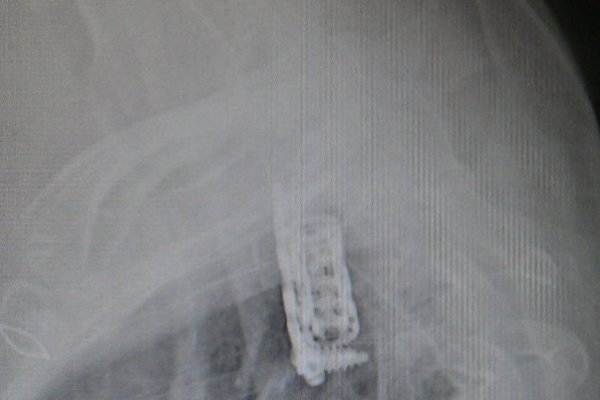

Professor Dr. M. Bülent Önal Gehirn und Nervenchirurgie